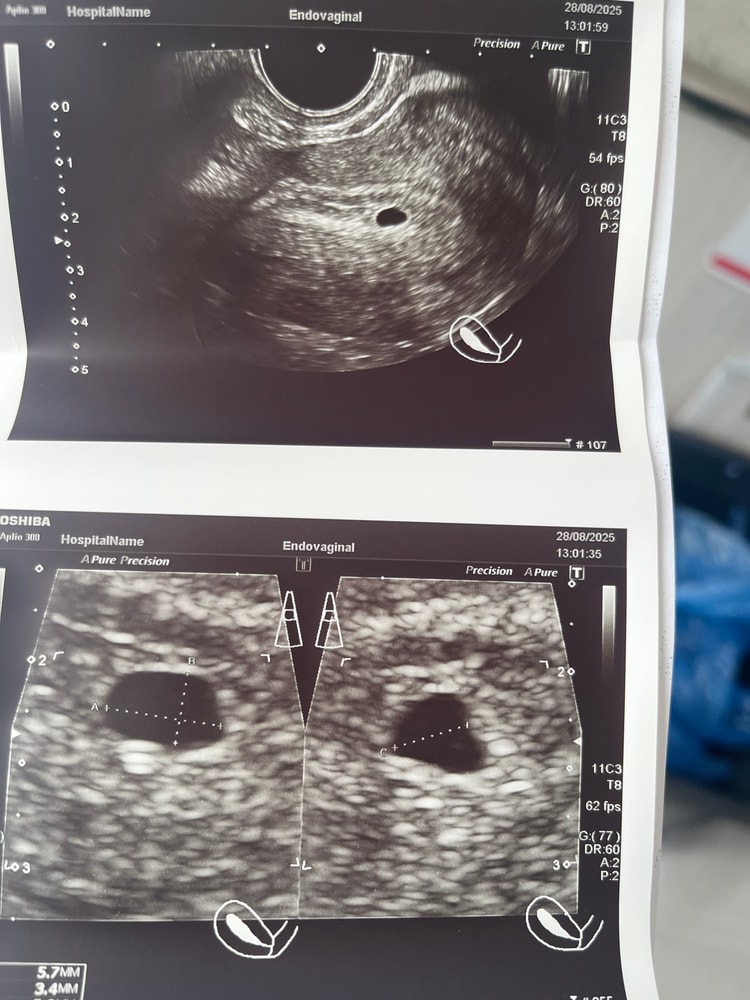

Альбина , у меня так было, в итоге потом увидели эмбрион, но без сердцебиения. Две замершие в итоге беременности. У вас уже должно всё быть видно и плодное яйцо слегка деформировано, это начало выкидыша. Желточного мешка нет на 7 неделе, тут без шансов.

В 6.5 недель не увидели эмбриона. Отправляют на чистку Большая разница между ХГЧ.